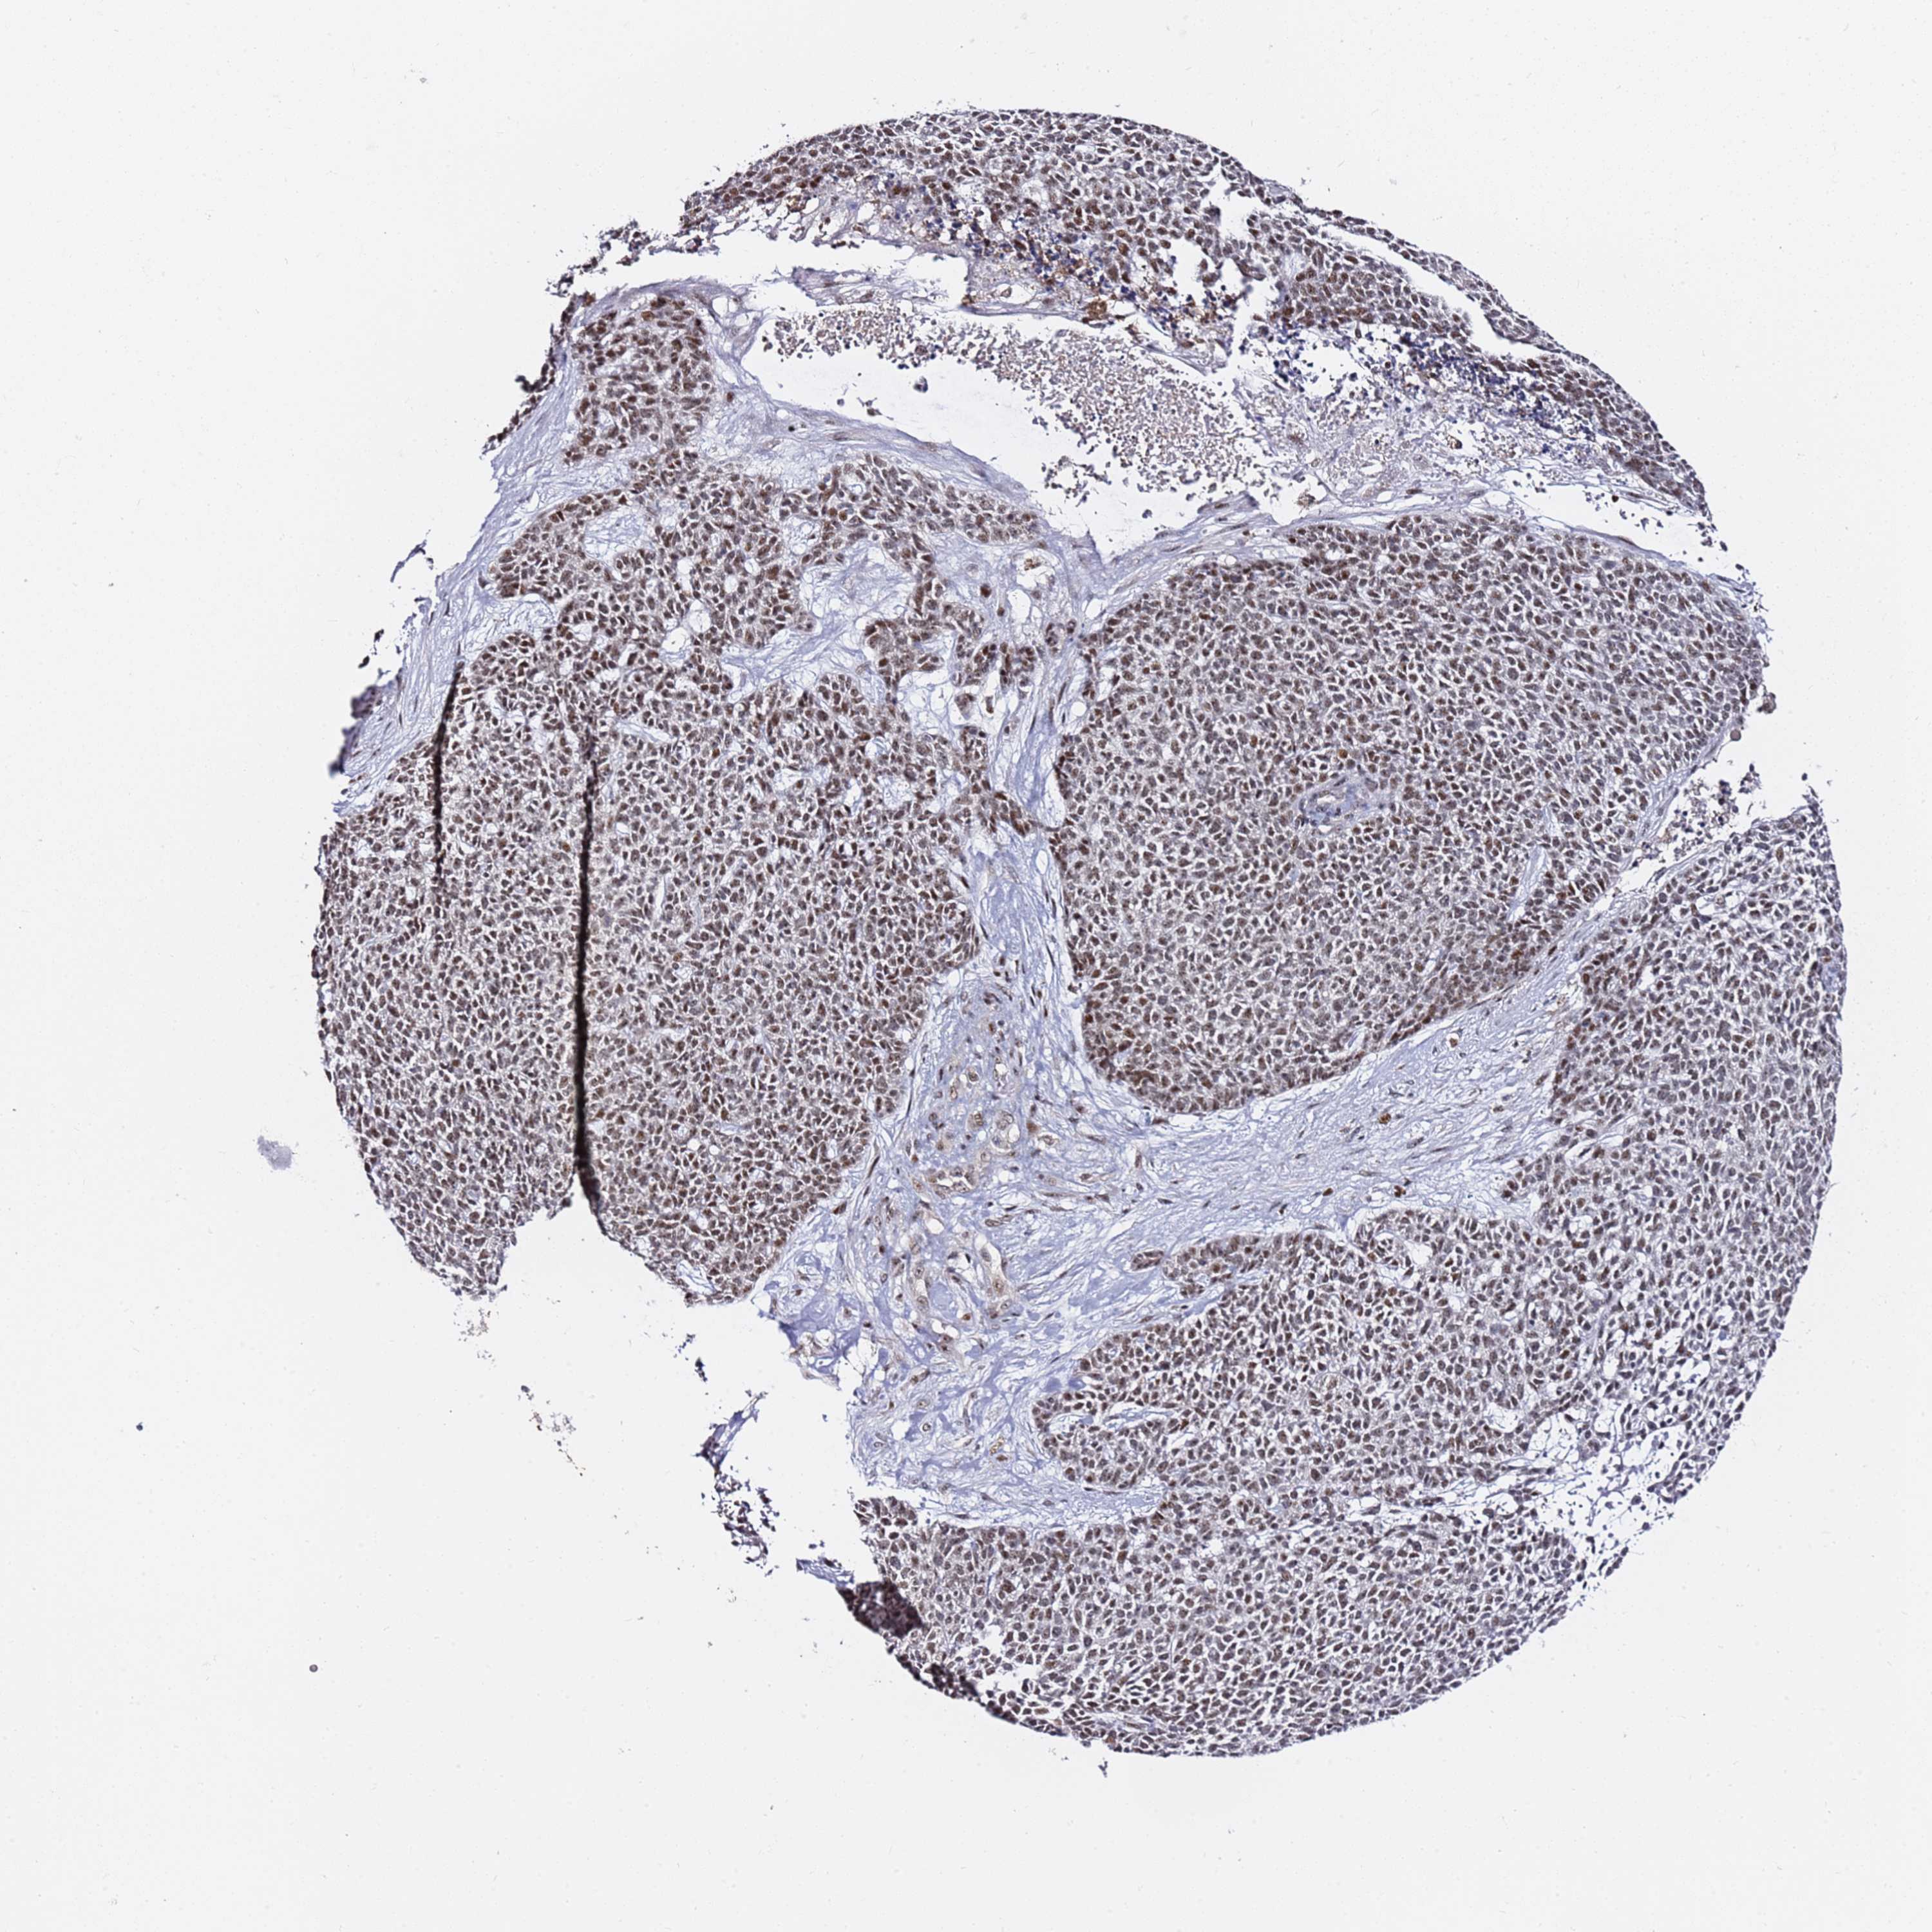

SKIN CANCER - Protein expressioni

A mouse-over function shows sample information and annotation data. Click on an image to view it in a full screen mode. Samples can be filtered based on level of antibody staining by selecting one or several of the following categories: high, medium, low and not detected. The assay and annotation is described here.

Each image is clickable and will lead to virtual microscopy that enables deeper exploration of all samples and also displays staining intensity scores, fraction scores and subcellular localization as well as patient and tissue information for each sample.

Antibody HPA046681

Staining

High

Intensity

Strong

Quantity

>75%

Location

Nuclear

Squamous cell carcinoma, metastatic, NOS

Squamous cell carcinoma, NOS